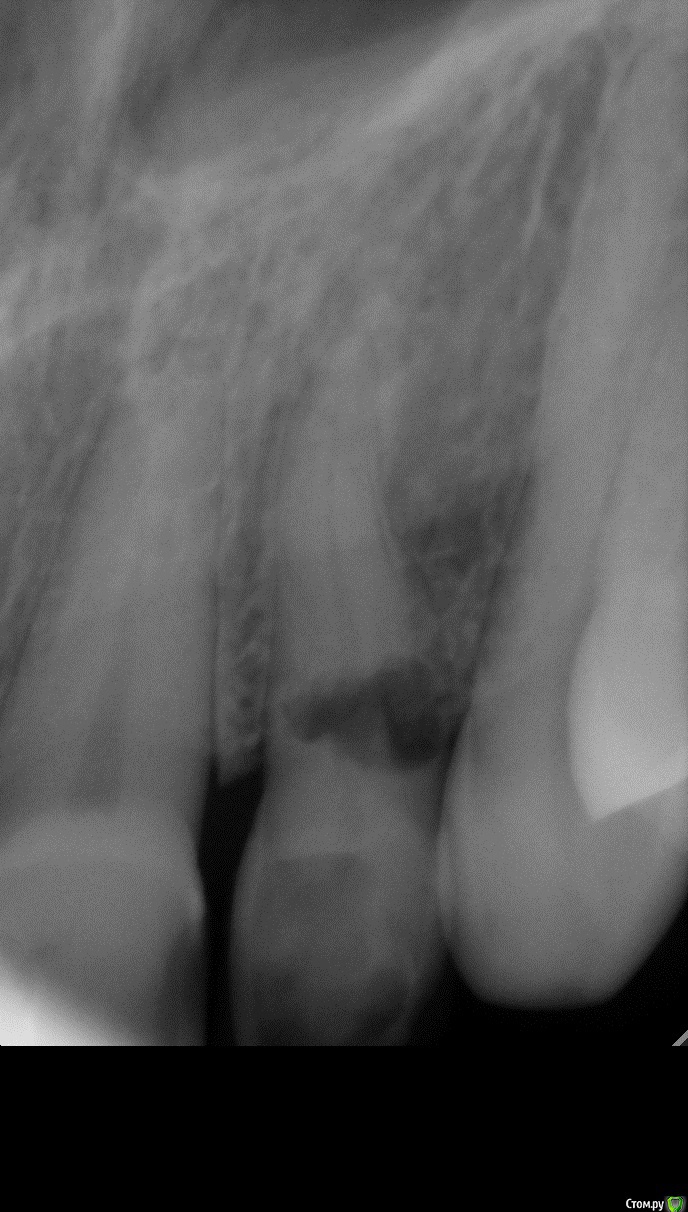

Sundance Опубликовано 10 июня, 2015 Автор Поделиться Опубликовано 10 июня, 2015 А в какой среде был зуб или его вообще не вынимали? Связок же уже не будет, будет "жесткое соединение" зуб-кость?удаляется полностю и ставится в том положение в каком надо ) самое важное атравматично и неприкасатся к остаткам связочного апарата на корне, они потом регенерируют Ссылка на комментарий

Sundance Опубликовано 10 июня, 2015 Автор Поделиться Опубликовано 10 июня, 2015 как удаляли, периотомом связку то рвем?да но на корне остаются места со связкой и чем их больше тем больше шансов что будет полное востановление приодонта , правда в етом случаи другая ситуация корень уходил под кость на 2 мм пришлось на недельку поставить ортодонтическую тягу и только после етого удалять Ссылка на комментарий